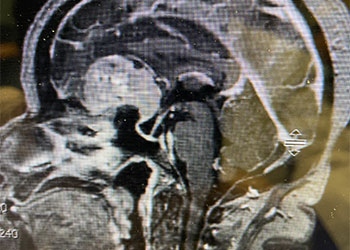

Brain:

Cerebral Metastases from Non-Small Cell Lung Cancer

Author: Xavier P. J. Gaudin D.O., F.A.C.O.S., Read More!